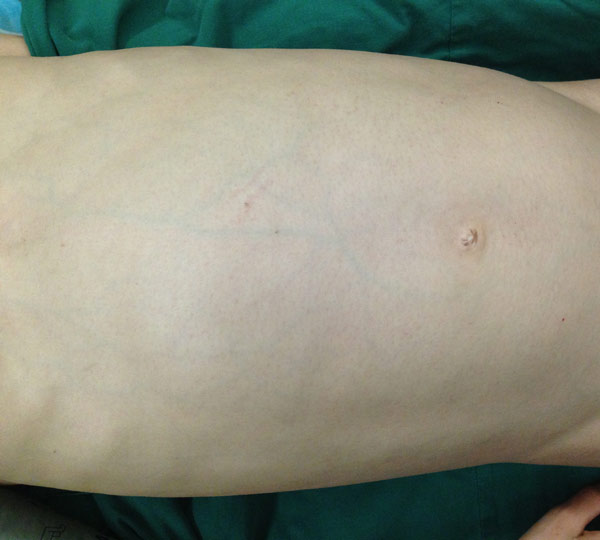

从外形上看,小黄瘦小的身躯大腹便便,貌似怀孕许久,与她年幼的面庞极不相乘。近日,小黄接受了手术治疗,医生成功为其切除了一个约7公斤的肿瘤,解除了伴随十年的“包袱”,术后经病理证实,小黄肚中包块为未成熟性畸胎瘤。

小黄肚大似有孕